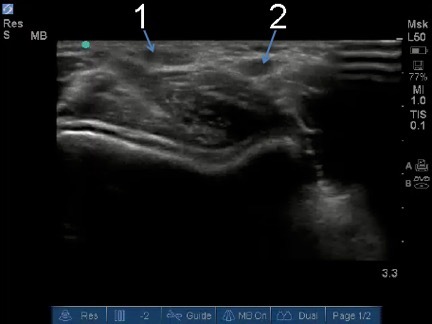

Elbow Distal Biceps Tendon Short Axis Image Distal Biceps Tendon Brachial Artery (before ulnar branch)